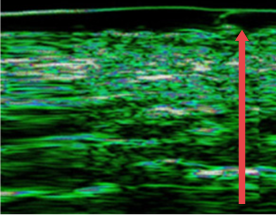

ก่อนฉีด

หลังฉีด 4 เดือน

หลังฉีด 7 เดือน

ปรับปรุงชั้นหนังแท้ของผิวหนังที่บางลงเนื่องจากความชรา การทำหัตถการผิวบ่อยๆ และการกระตุ้นจากภายนอก

(ชั้นหนังแท้หนาขึ้น 12%)

(ชั้นหนังแท้หนาขึ้น 27% )